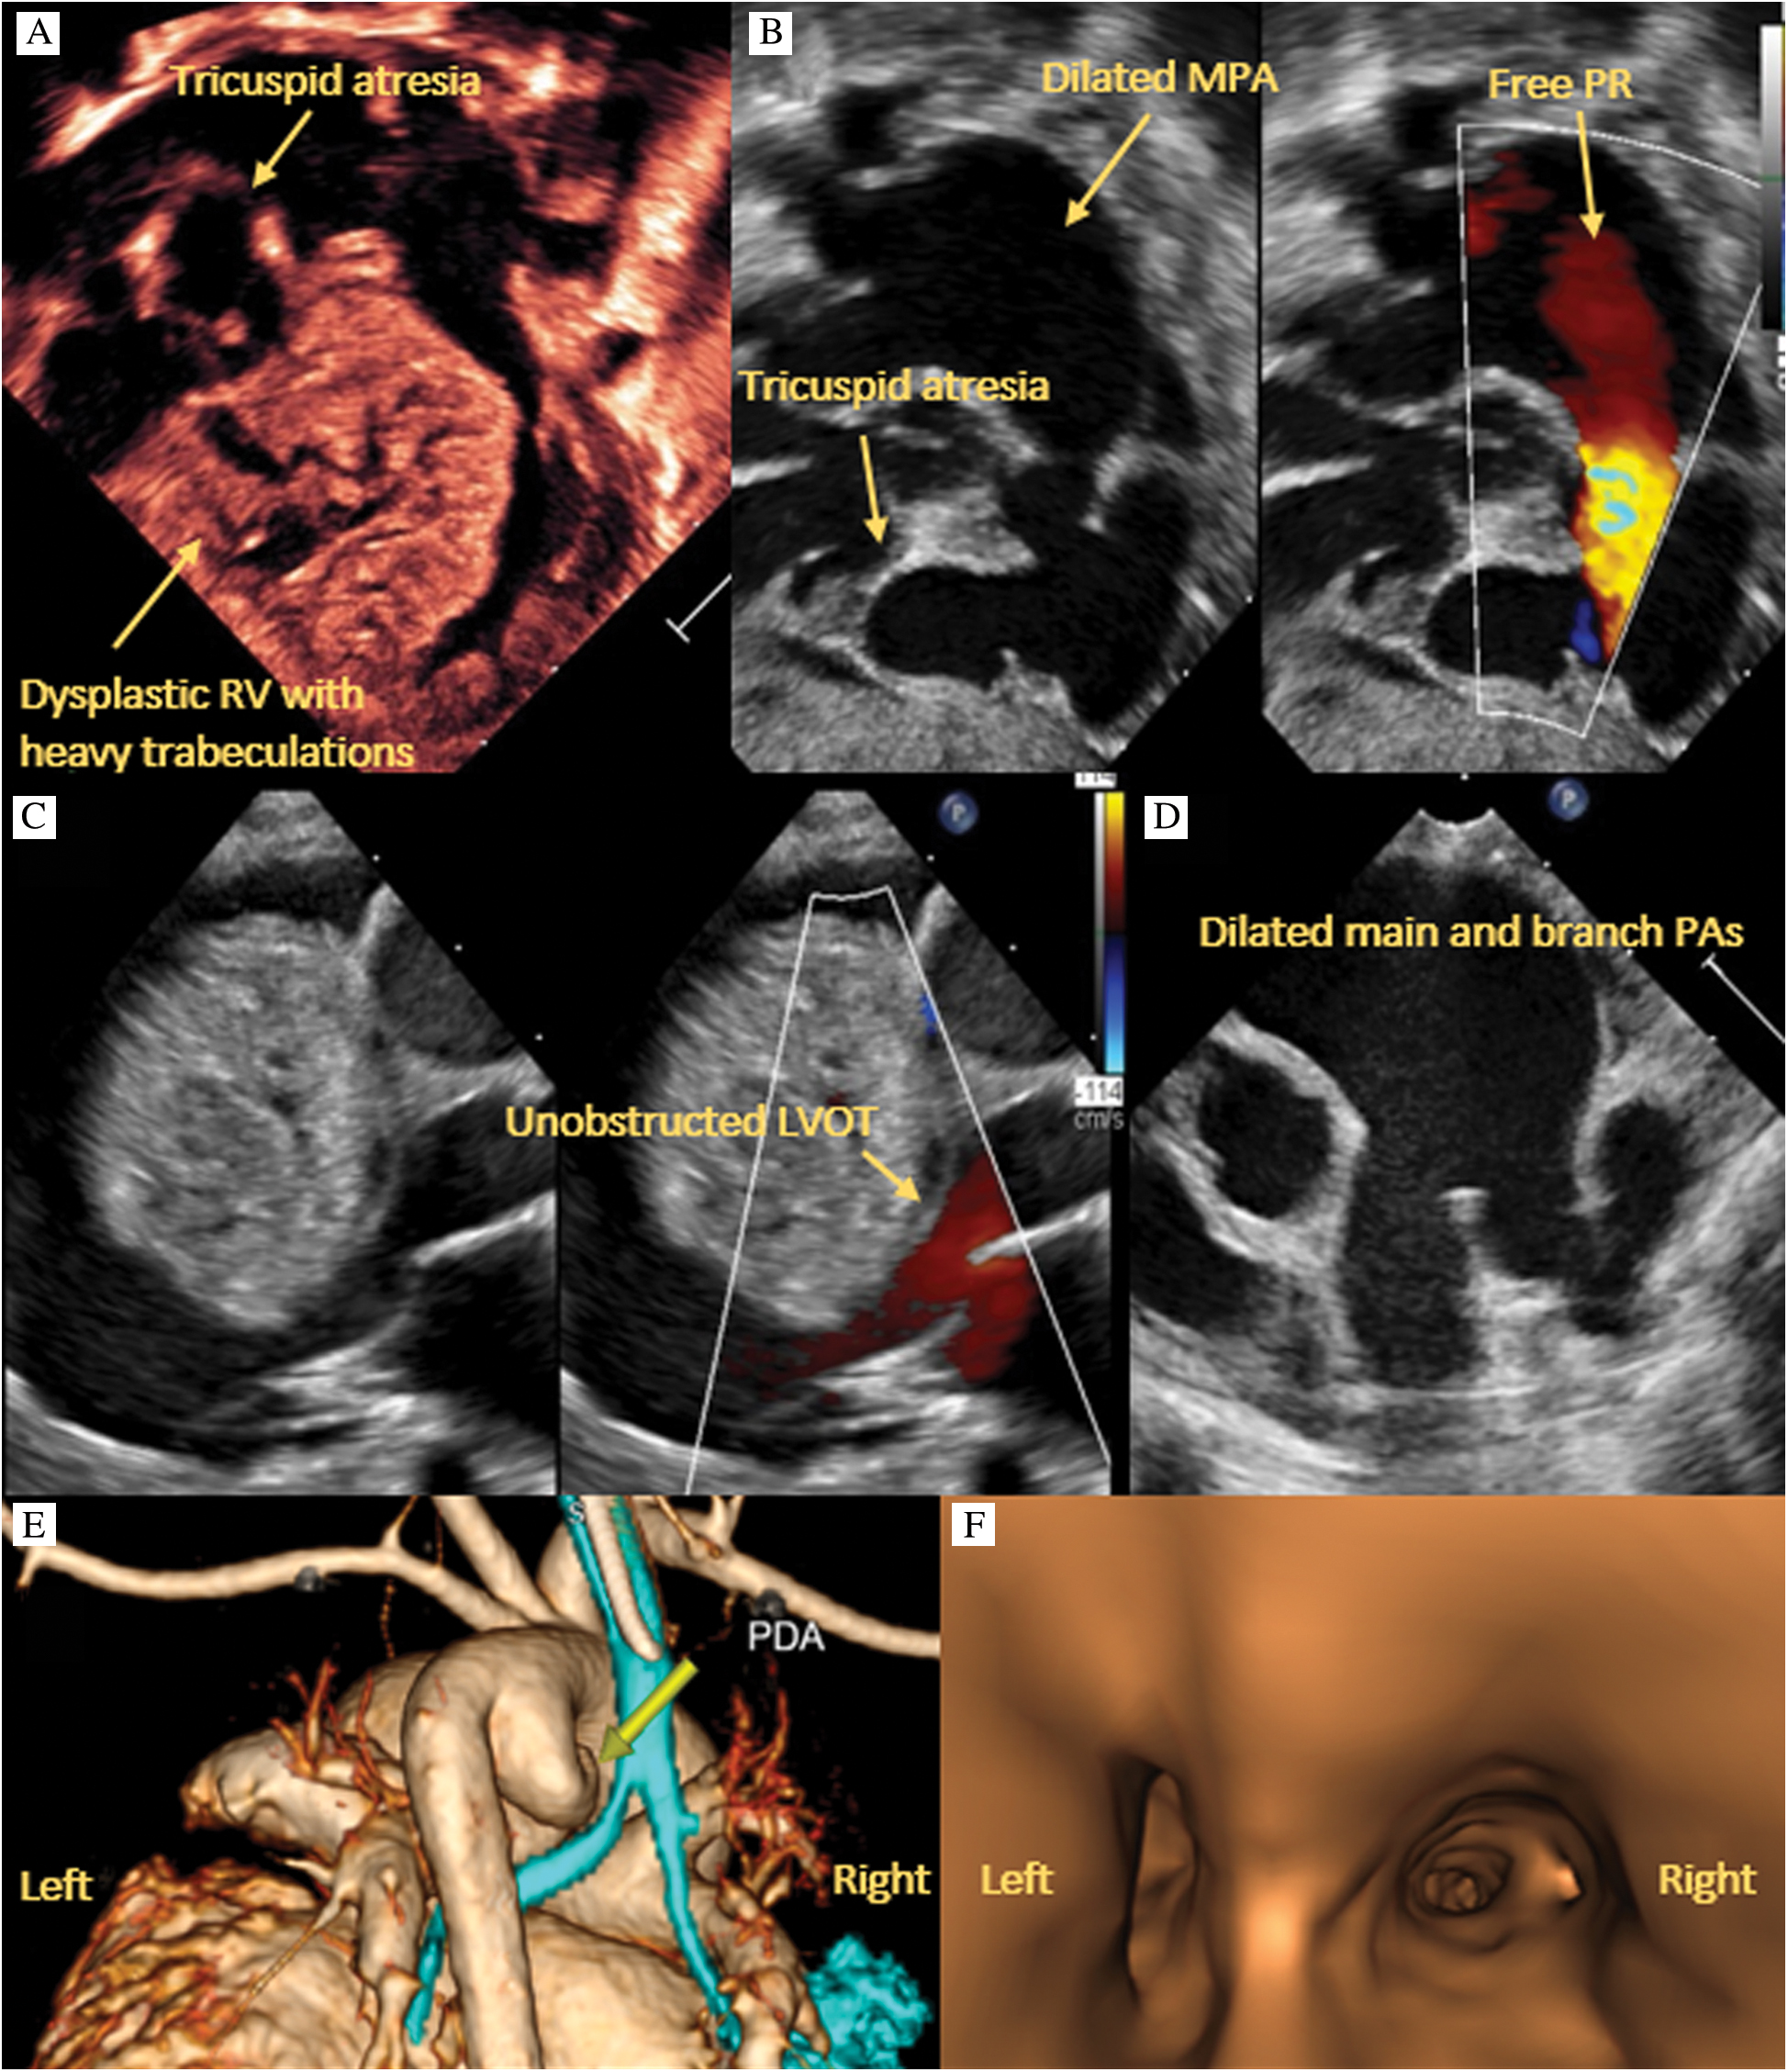

Delivery was scheduled at the closest birthing center with the surgical team prepared to initiate extracorporeal membrane oxygenation. At 39 weeks gestation, he underwent elective cesarean section. Birth weight was 3 kilograms. The infant was born limp and cyanotic. APGAR scores were 2, 5 and 5, at 1, 5 and 10 minutes respectively. He ultimately required intubation, epinephrine and prostaglandin, and was briskly transferred to the cardiac intensive care unit. Postnatal transthoracic echocardiogram revealed APVS with free pulmonary regurgitation and markedly dilated pulmonary arteries, near membranous TA, an enlarged and dysplastic RV with compression of the LV, no LV outflow tract obstruction, mildly depressed LV systolic function and a large, tortuous patent ductus arteriosus (PDA) with right to left flow in systole and left to right in diastole (Figs. 2A–2D).

Figure 2: Transthoracic echocardiography. A: 4 chamber view of near membranous tricuspid atresia and a large, dysplastic RV with multiple trabeculations. B: Right anterior oblique view of absent pulmonary valve with free regurgitation as well as thin walled RV inflow and outflow tracts. C: Parasternal long axis view of large, dysplastic RV impinging on the LV but without obstruction. D: Parasternal short axis view of dilated main and branch pulmonary arteries. E: CTA 3D reconstruction showing compression of the left mainstem bronchus. F: CT airway reconstruction showing left bronchus narrowing due to external compression

After extensive discussion and review of published case reports, palliation with main pulmonary artery ligation and placement of a Blalock-Thomas-Taussig shunt seemed plausible. CTA confirmed profound dilatation of the main and branch pulmonary arteries. While the trachea was of normal caliber, there was marked compression of the left mainstem, bilateral upper lobe and right lower lobe bronchi (Figs. 2E–2F). The significant bronchial compression and anasarca prohibited weaning of ventilatory support. Further, idioventricular tachycardia, managed with lidocaine and amiodarone due to breakthrough episodes, contributed to a low cardiac output state. Genetic evaluation ultimately revealed a heterozygous variant in the desmoplakin (DSP) gene. This particular variant has not been previously reported. However, the pathogenic variant in DSP is associated with autosomal dominant familial arrhythmogenic RV dysplasia (ARVD) and dilated cardiomyopathy. After extensive discussion regarding the unknown prognosis and potential comorbidities, the parents opted to withdraw care.